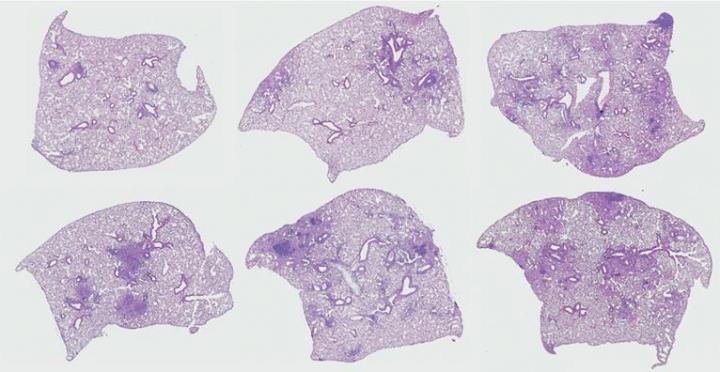

image: Elderly alveolar lining fluid-exposed Mycobacterium tuberculosis (Mtb) demonstrates increased Mtb-induced immunopathology in the lung.

When the same experiment was conducted in vivo in healthy young mice, results recapitulated what happened in the in vitro experiment. The animals that received Mtb that had been incubated in lung lining fluid from older humans could not control the infection as well as animals that received Mtb incubated with lung lining fluid from a younger person.